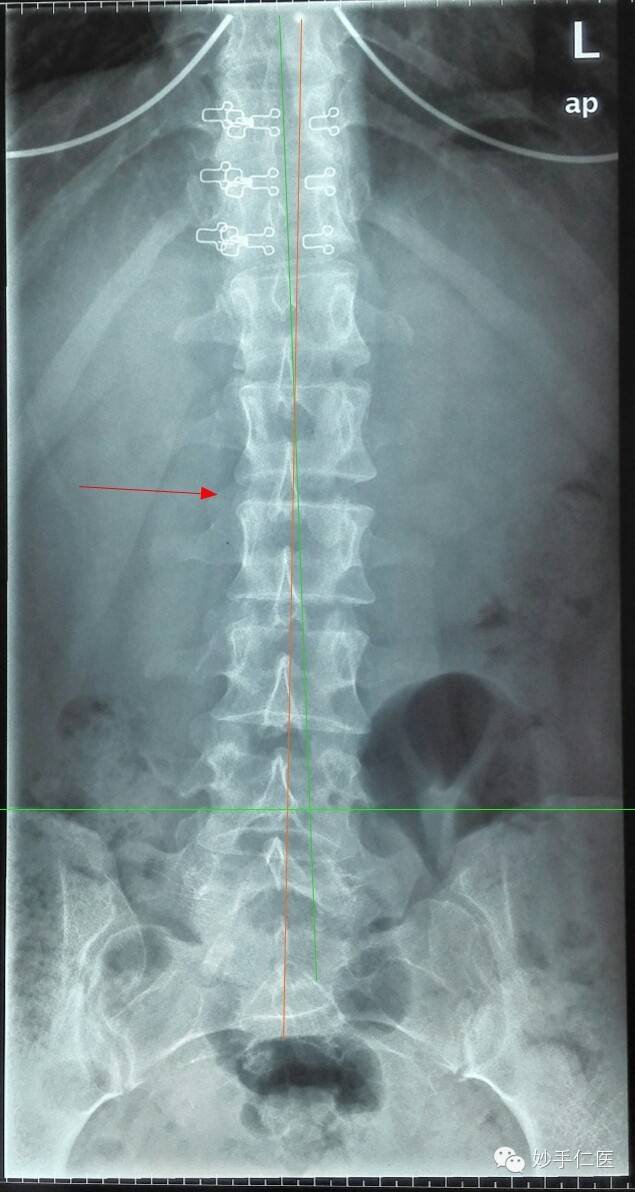

腰椎正位片子:腰椎存在脊柱侧弯,腰椎存在棘突旋转的状况,双侧髂骨高度不一致。腰椎和骨盆的片子,清晰的表明了人体力学结构的失稳,导致从腰部向上部分的力学状态破坏。通常来说,腰部问题和颈部问题都是存在联合出现的状况,毕竟,从根源来说,只是人体整体力学状态失稳的不同体现。